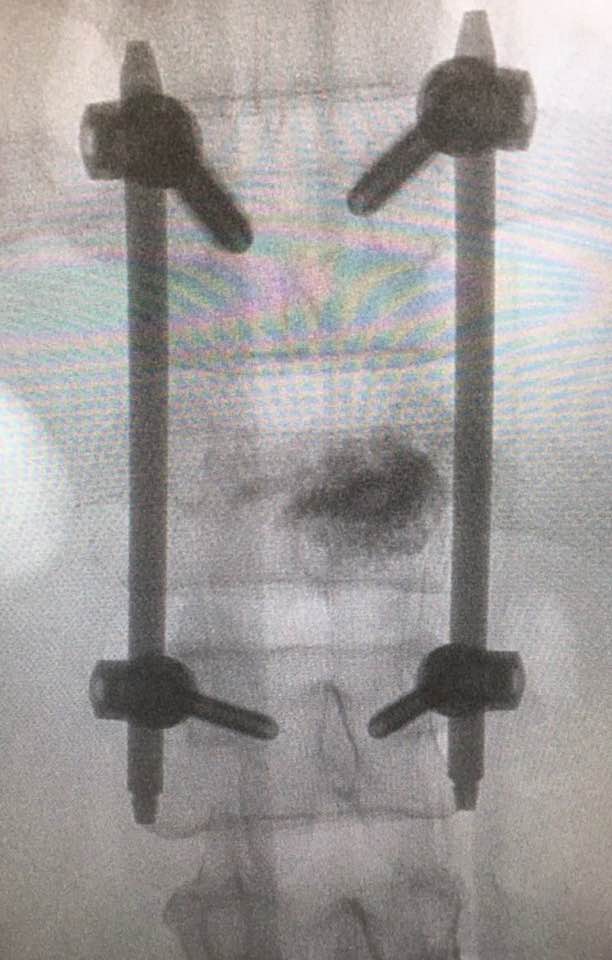

嚴重的工業意外受傷,T12胸脊椎不穩定的3段(前、中、後柱列)壓迫性脊柱椎體骨折

1. 即使您的胸部及胸脊椎柱被8英尺高和200磅重的巨大雪櫃嚴重壓碎, 您仍然生存, 您的中樞脊髓神經但沒有受到傷害.

2. 即使公立醫院忽畧了你不穩定的前、中、後3柱列的T12胸脊椎骨折,並在3天後容許你出院送回家, 你到私家醫院再進行第二次詳細檢查!

3. 幸運的是,入院前及兩天來你未有因為不穩定的脊柱椎體骨折碎片的移位而導致你脊髓中樞神經到不可逆轉和永久性的損傷致雙腿癱瘓及大小便失禁. 今天所有穩定你碎裂脊椎的手術都做完了.